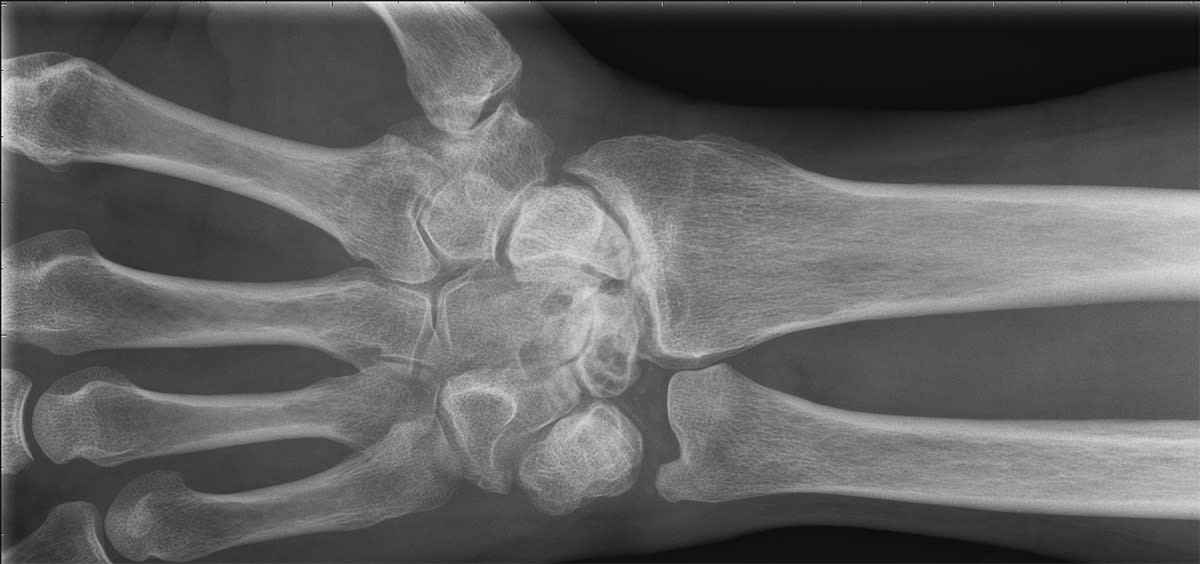

Röntgenbilden visar en handled som är totalförstörd på grund av avsaknad av brosk. Tack vare operationsmetoden handledsdenervation slapp patienten stelopereras och är idag smärtfri.